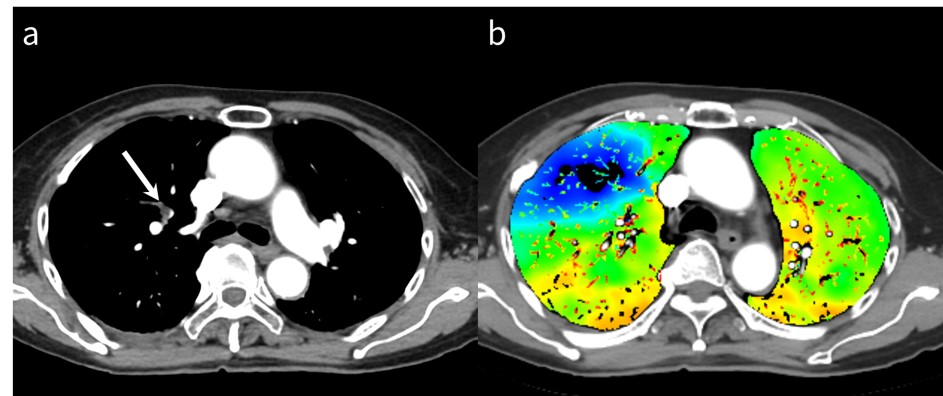

RevolutionApexElite_Gifu02_06.jpg

図5 肺動脈血栓塞栓症症例

a: 胸部造影CT

b: ヨード密度画像

胸部造影CTで右肺動脈に血栓を認める(→)。ヨード密度画像では塞栓領域の血流低下が一目瞭然である。

物質弁別画像に用いられるMaterial DataにはIodine, Water, Calcium, Hydroxyapatite (HAP), Uric Acid, Fat等が存在する。これらの物質のペアにより物質弁別画像が再構成され、組織の構成要素や造影剤分布等、定性的かつ定量的な情報をもたらしてくれる。このうち一般的に臨床で用いられる画像はIodine/Water画像であり、いわゆるヨード密度画像と呼ばれるものである。この画像を構成する物質はヨードと水のみであると仮定し、水を基準としてどれくらいのヨードが存在するかを表した画像とも言えよう。これによりヨード密度画像では一目で組織の造影効果を視認することができ、肺動脈血栓塞栓症評価に使用されるイメージが強いのではないだろうか(図5)。

このように定性画像としてももちろん有用であるが、mg/mLで表示されるヨード密度値を計測できる点も、病変の悪性度評価や治療効果予測、予後予測に応用が可能と報告されている通り、Single Energy CT撮像では得られない付加価値をもたらす。